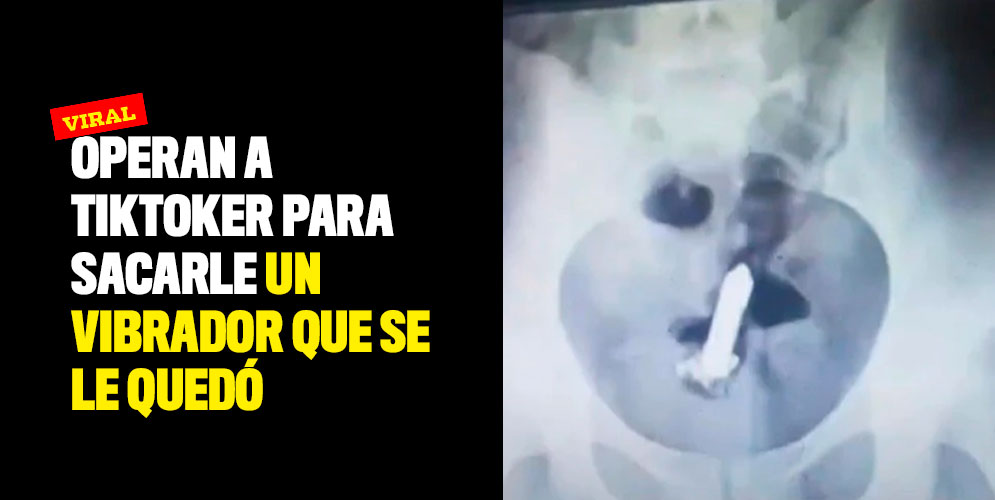

Luego de realizarle algunos exámenes lograron determinar el lugar exacto donde estaba el objeto, como no era posible alcanzarlo manualmente la entraron al quirófano.